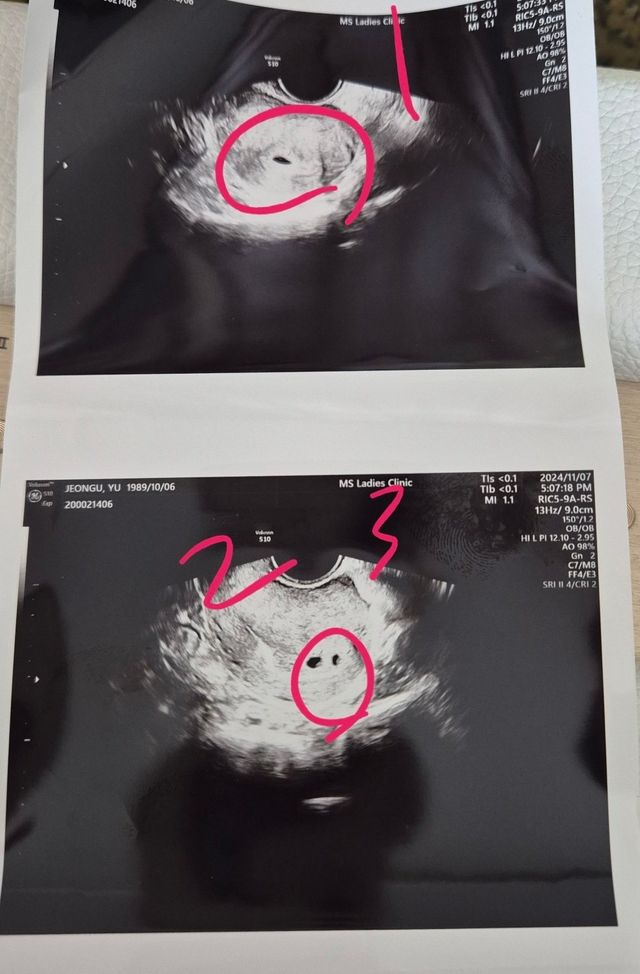

지난주에 애기집을 보고 왔는데 애기집이 세개 있답니다.

이대로 건강하게 자라면 세 쌍 둥 이